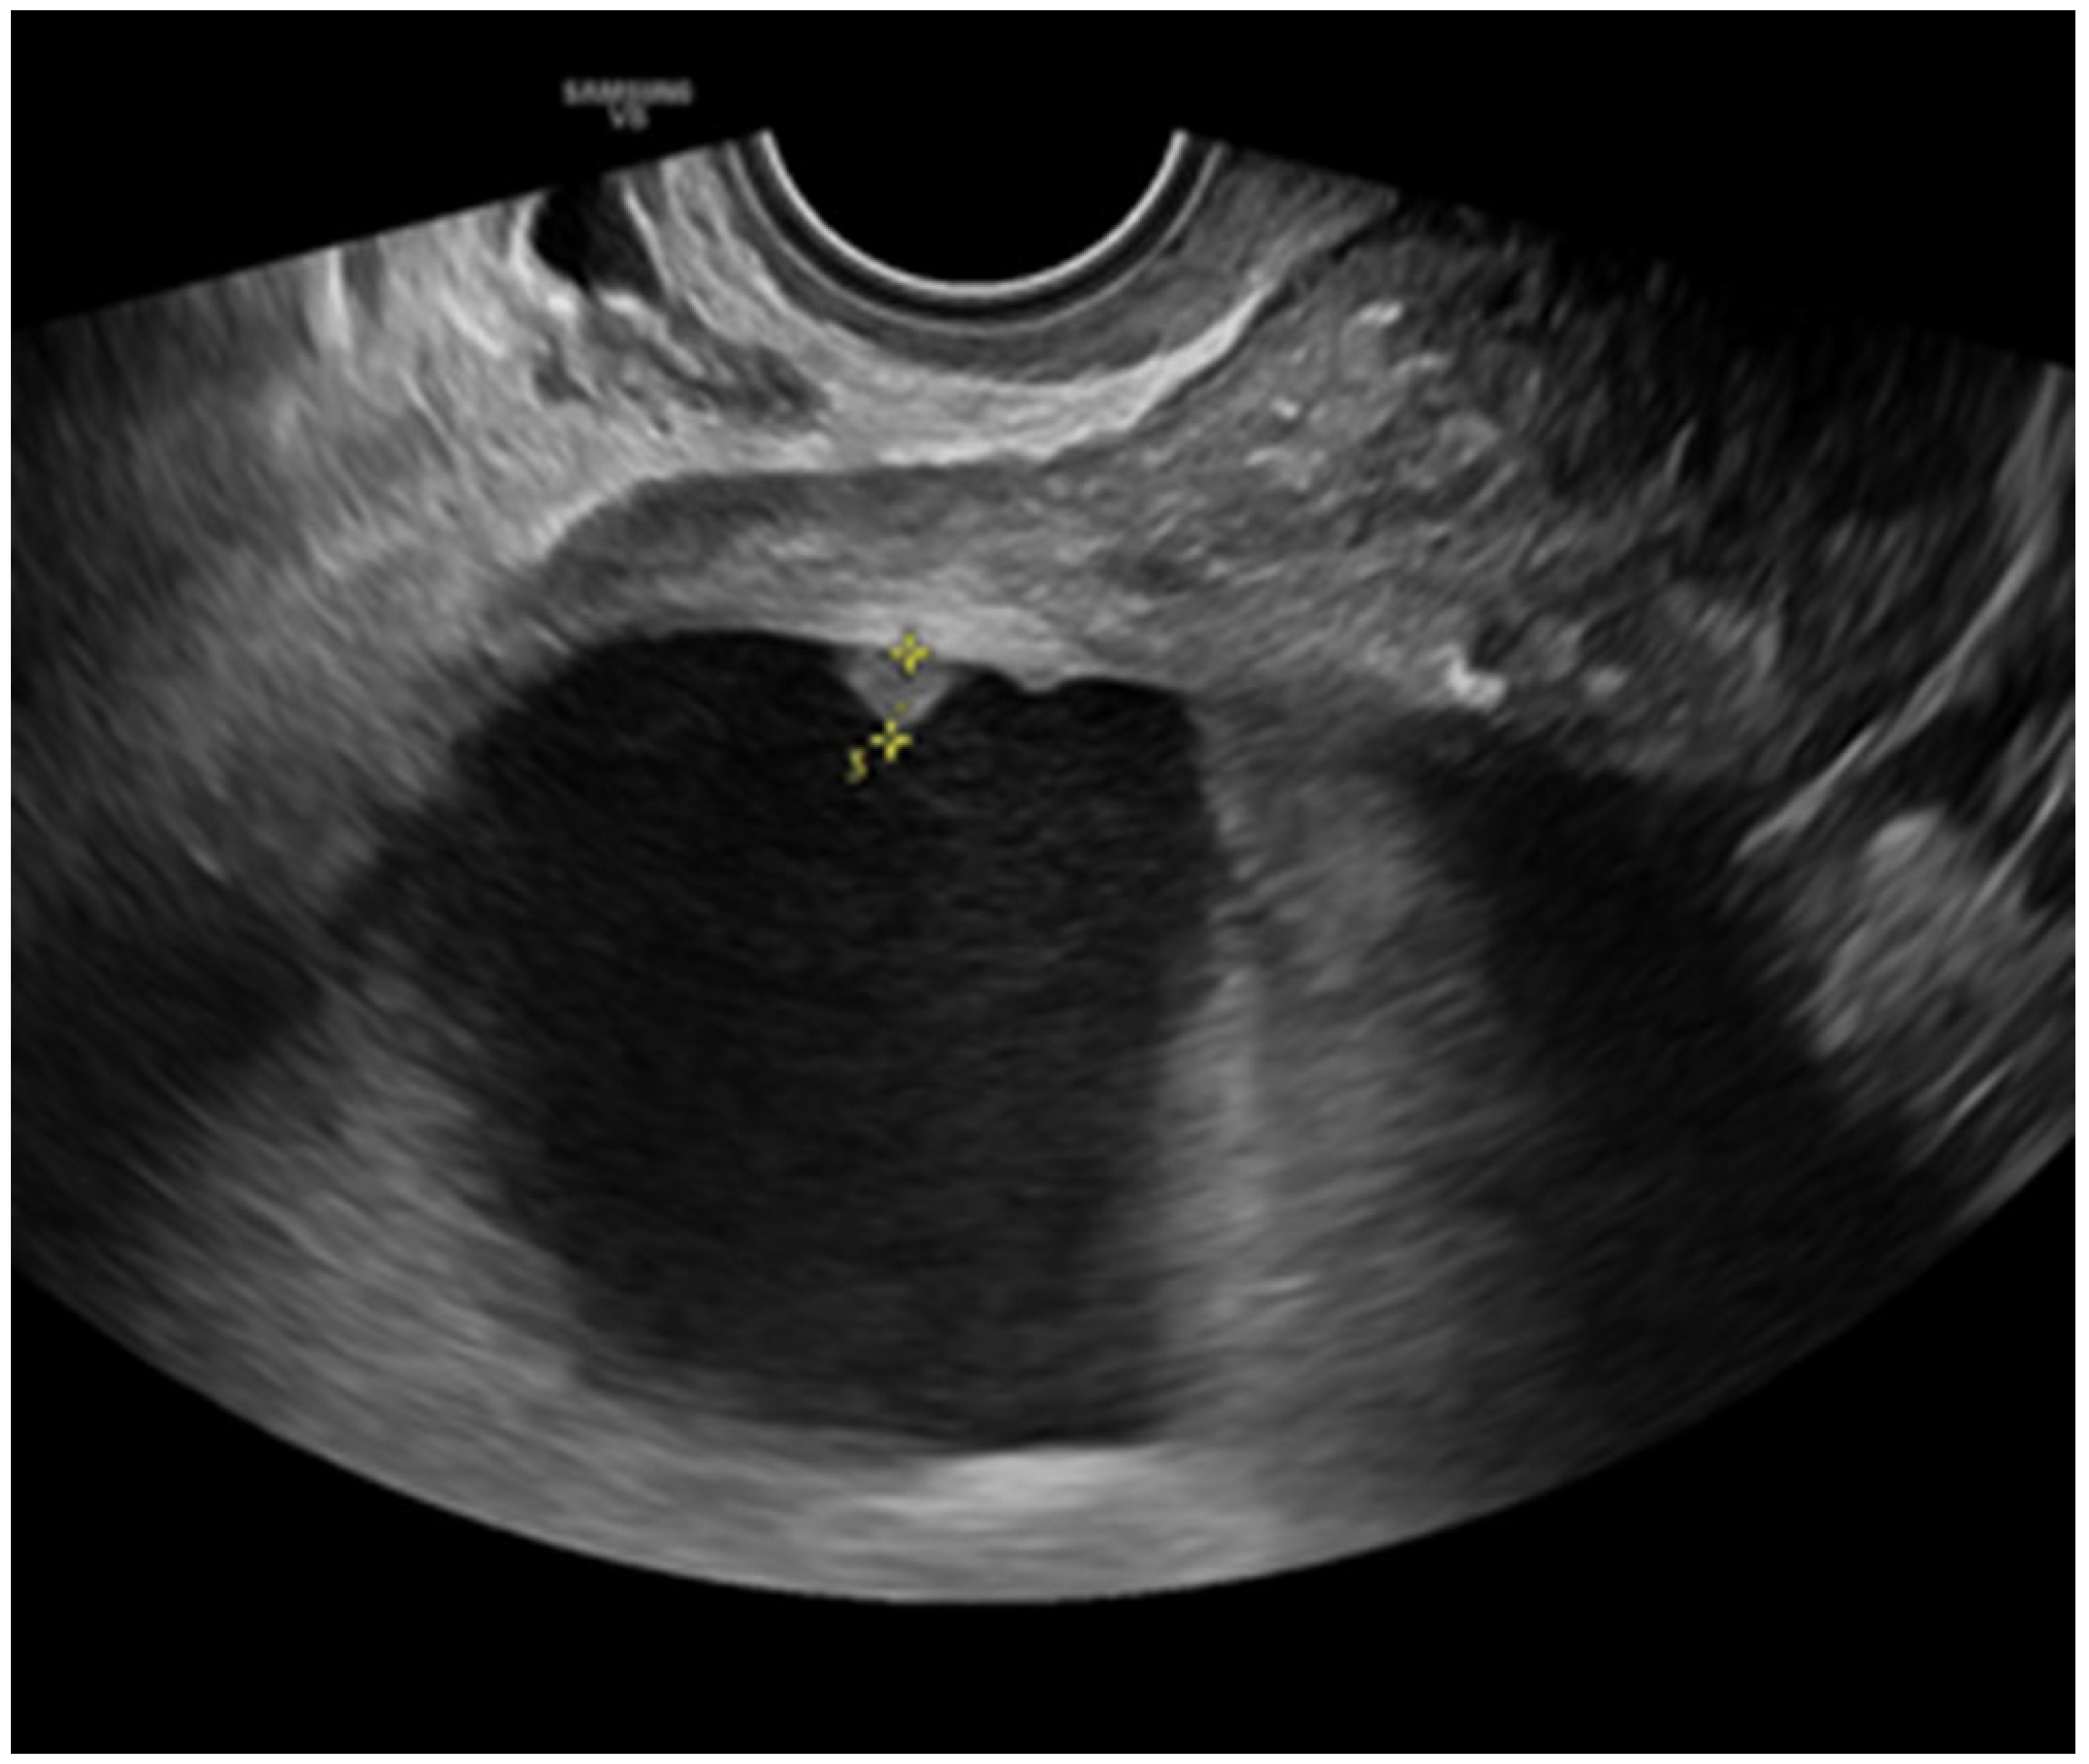

- Savelli, L.; De Iaco, P.; Ceccaroni, M.; Ghi, T.; Ceccarini, M.; Seracchioli, R.; Cacciatore, B. Transvaginal sonographic features of peritoneal carcinomatosis. Ultrasound Obstet. Gynecol. 2005, 26, 552–557. [Google Scholar] [CrossRef]

- Weinberger, V.; Fischerova, D.; Semeradova, I.; Slama, J.; Dundr, P.; Dusek, L.; Cibula, D.; Zikan, M. Prospective Evaluation of Ultrasound Accuracy in the Detection of Pelvic Carcinomatosis in Patients with Ovarian Cancer. Ultrasound Med. Biol. 2016, 42, 2196–2202. [Google Scholar] [CrossRef]

- Zikan, M.; Fischerova, D.; Semeradova, I.; Slama, J.; Dundr, P.; Weinberger, V.; Dusek, L.; Cibula, D. Accuracy of ultrasound in prediction of rectosigmoid infiltration in epithelial ovarian cancer. Ultrasound Obstet. Gynecol. 2017, 50, 533–538. [Google Scholar] [CrossRef]

- Fischerova, D.; Zikan, M.; Semeradova, I.; Slama, J.; Kocian, R.; Dundr, P.; Nemejcova, K.; Burgetova, A.; Dusek, L.; Cibula, D. Ultrasound in preoperative assessment of pelvic and abdominal spread in patients with ovarian cancer: A prospective study. Ultrasound Obstet. Gynecol. 2017, 49, 263–274. [Google Scholar] [CrossRef]